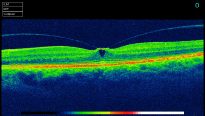

A 3D section of the layers ofthe retina and vitreous jellyA 3D section of the layers of the retina and vitreous jellyAge-related Macular Degeneration Dry FormAge-related Macular Degeneration Dry FormAge-related Macular Degeneration Wet FormAge-related Macular Degeneration Wet FormThe vitreous (jelly) pulling on the retinaThe vitreous (jelly) pulling on the retinaImage of Retina (back of the eye)Image of Retina (back of the eye)